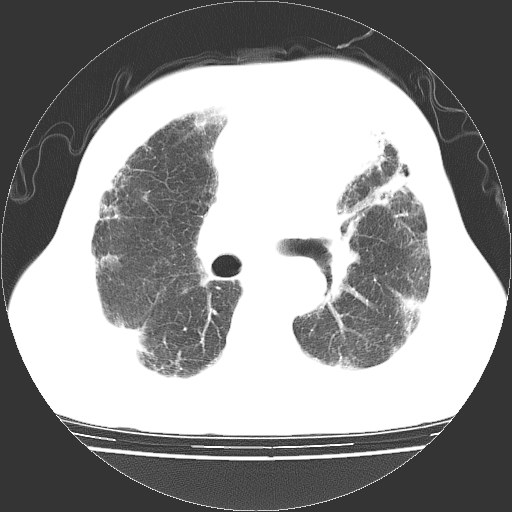

标题: CT25149:男,69岁,反复咳嗽、咳痰五年余,呼吸困难三天。 [打印本页]

男,69岁,反复咳嗽、咳痰五年余,呼吸困难三天。

慢支伴感染、肺气肿、肺心病

慢支伴感染、肺气肿、肺心病!支持!另:间质纤维化!

两肺间质性炎症并感染,左上叶肉芽肿

考虑慢性间质性肺炎并肺间质纤维化。

慢支伴感染、肺气肿、肺心病。双肺间质性改变(间质纤维化)。